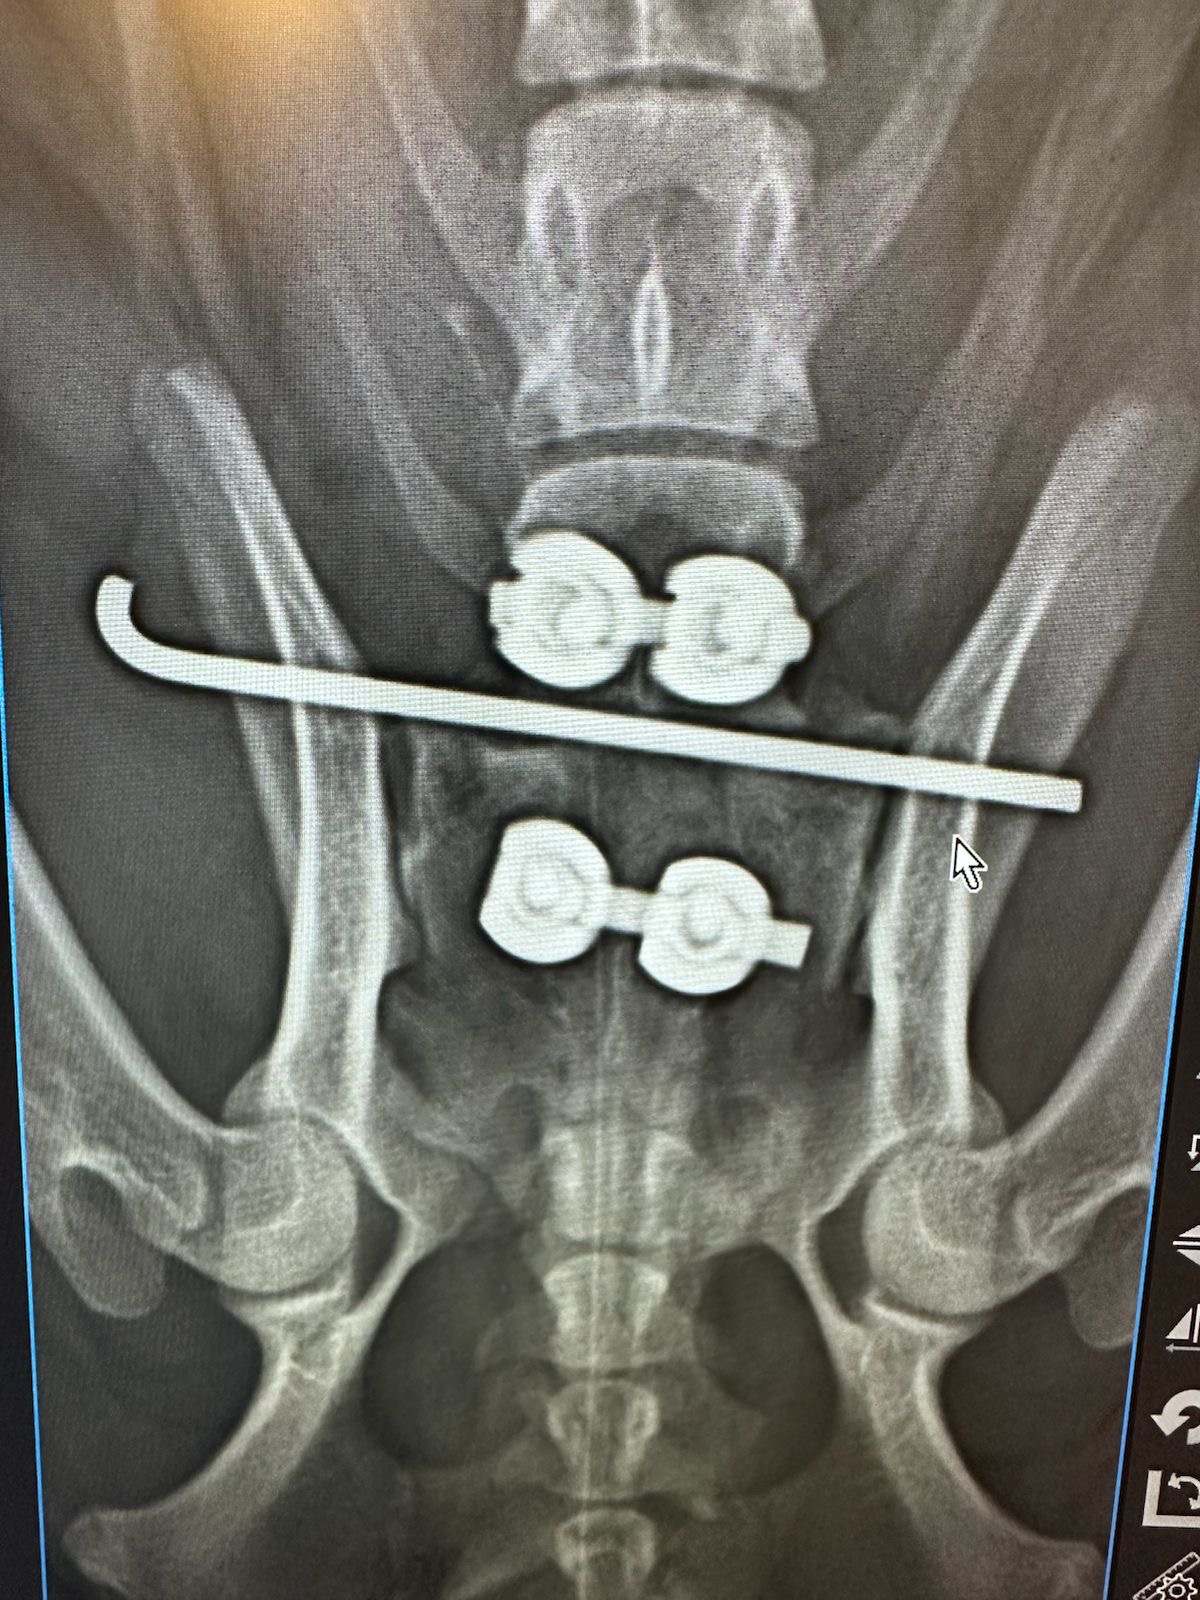

Rayos X y Ultrasonido

Dentro de CENEV contamos con especialistas dedicados al área de imagenología, dedicados al diagnóstico por pruebas como ultrasonido abdominal, radiología de tórax y abdomen, entre otras.

Nuestros equipos y personal especializado permiten estudios rápidos y de alta calidad para apoyar el diagnóstico clínico.